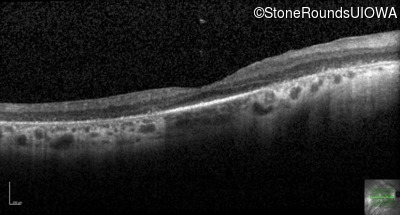

Optical Coherence Tomography - Left - 20/70 +1

Exemplar / OCT Stack

OCT Stack